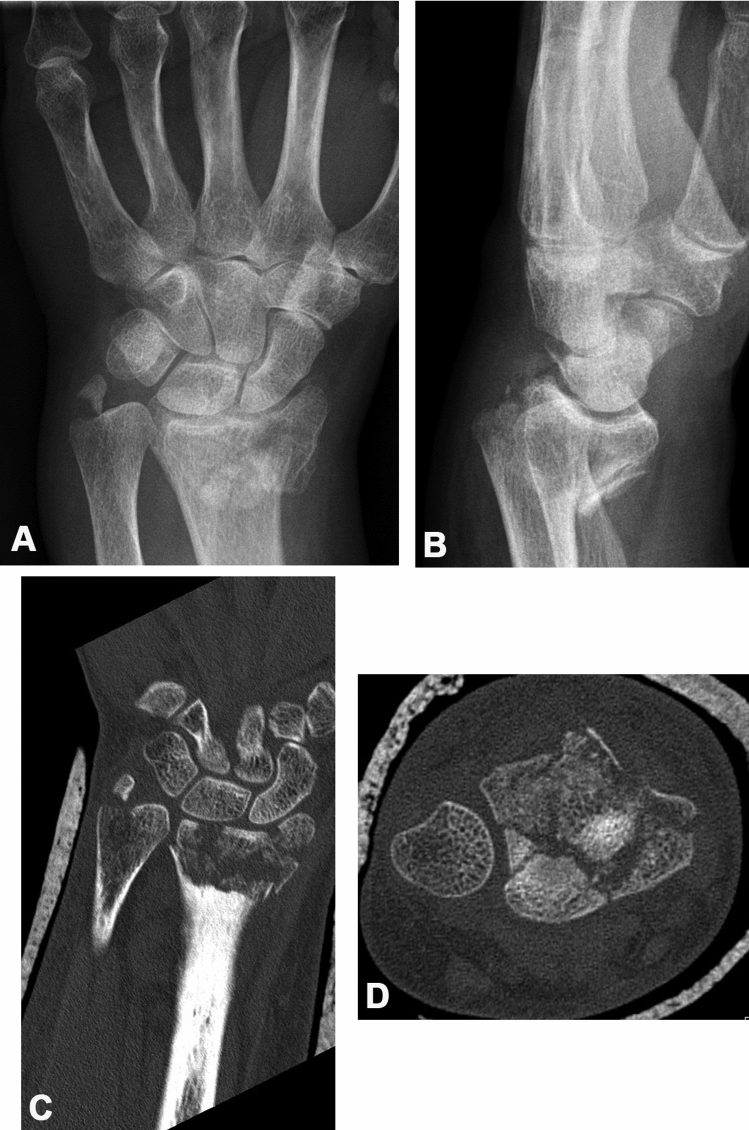

Fig. 1.

Distal radius fracture in a 63-year-old female patient. Considering the posteroanterior (a) and lateral (b) projections of plain film radiography, this fracture was classified as an extraarticular A2 fracture according to the AO/OTA classification. In the coronal (c) and axial (d) CT reconstructions, however, radiocarpal joint involvement was clearly identified

The distribution of recognized fracture extensions into the DRUJ comparing radiographs and CT scans was analyzed using the Frykman classification, since this is the only classification evaluating its involvement. Creating fourfold tables, the results for the same two observers were compared (see Table 3). The sensitivity of the standard radiographic assessment to identify DRUJ involvement was 33.3% for observer 1 and 38.3% for observer 2. When CT scans were considered as the reference, the false-negative rate of standard radiographs for DRUJ involvement therefore was 66.6% and 61.7%, respectively, and the test’s accuracy was 39.6% and 45.8%, respectively. Figure 2 shows a case, where extension of the fracture into the sigmoid notch was not seen on standard radiographs, however, was obvious when coronal and axial CT reconstructions were evaluated.

Fig. 2.

Distal radius fracture in a 61-year-old female patient. Using standard posteroanterior (a) and lateral (b) radiographs, this fracture was classified as a type IV fracture according to the Frykman classification. The coronal (c) and axial (d) CT reconstructions, however, clearly show fracture extension into the sigmoid notch